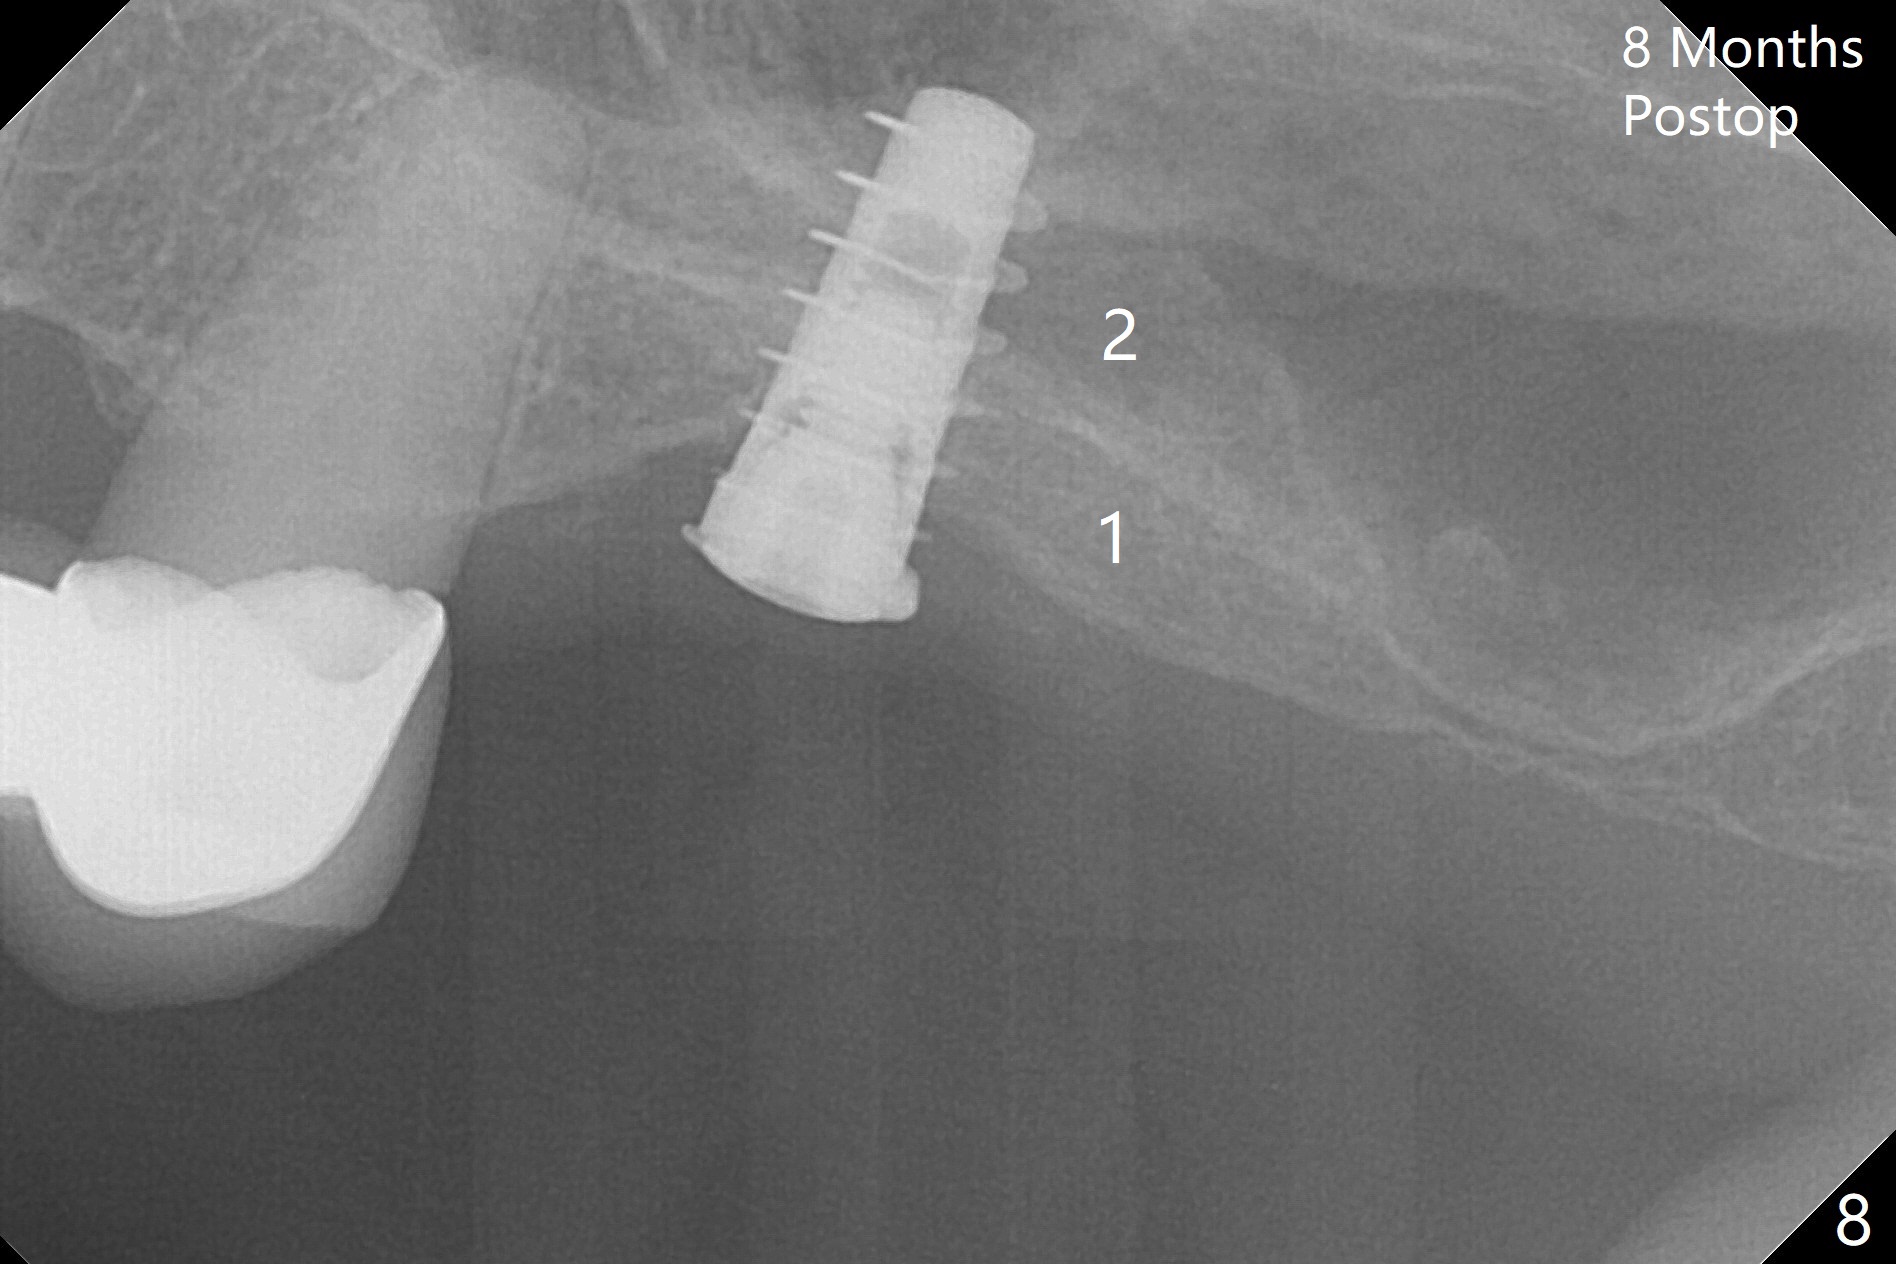

There are two layers of the bone, one (1) being denser than the other (2) 8 months postop (Fig.8). After local anesthesia, the healing screw is removed; the implant is found to be stable. A 6x4(2) mm pair abutment cannot be inserted due to blockage of the mesiobuccal gingiva (Fig.9 *). Instead a 6x2 mm healing abutment is placed. Since the implant is placed too superficial, use a 1 mm cuff abutment.